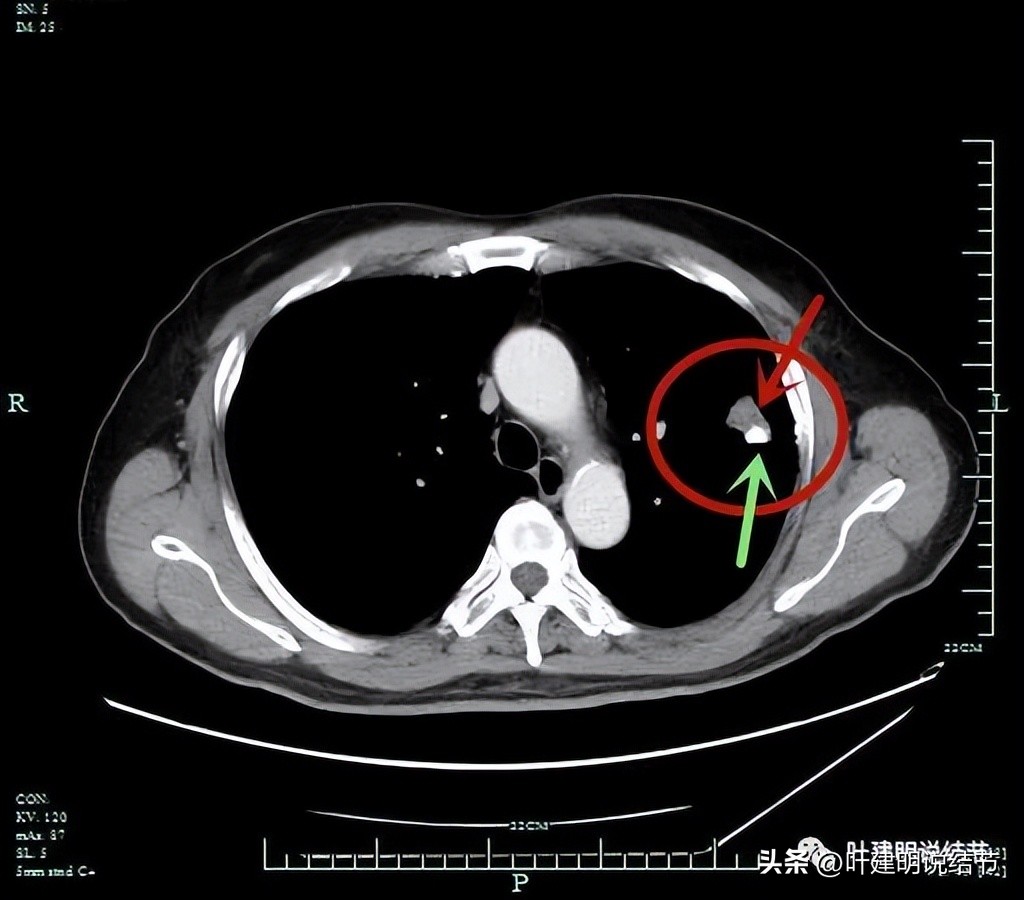

平扫纵隔窗见病灶伴有钙化(绿色箭头)

增强CT见病灶处的样子。

有钙化是不是考虑良性的呢?一般来说病灶伴钙化容易是良性,但这个病例恶性的影像太多太明显,所以再来看PET影像:

肺穿刺:红色箭头示病灶;绿色示穿刺针。

穿刺致气胸。